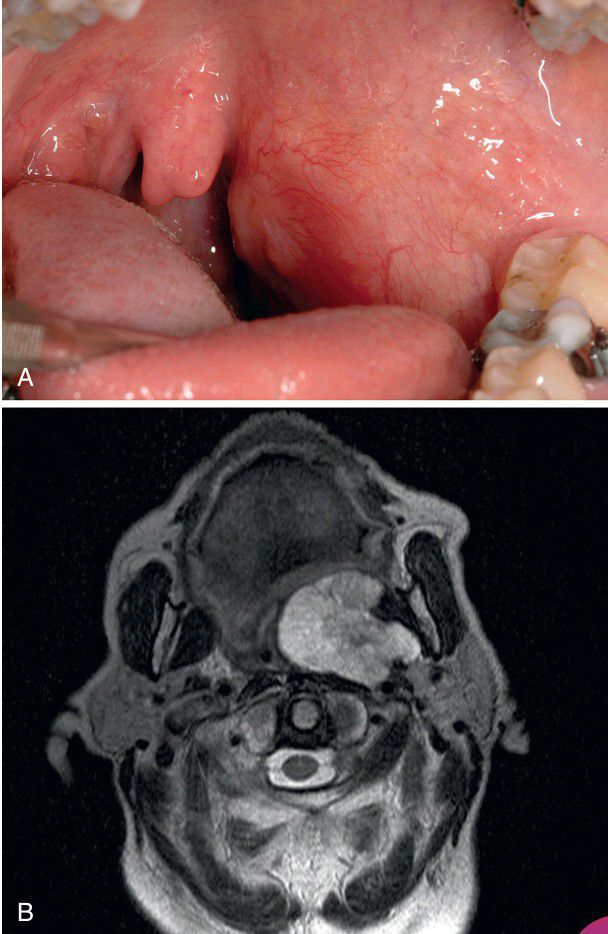

Pleomorphic Adenoma

. A, Large tumor from the deep lobe of the parotid gland, which has resulted in a firm mass of the lateral soft palate. B, Contrast-enhanced axial magnetic resonance image (MRI) of a tumor of the deep lobe of the parotid gland.